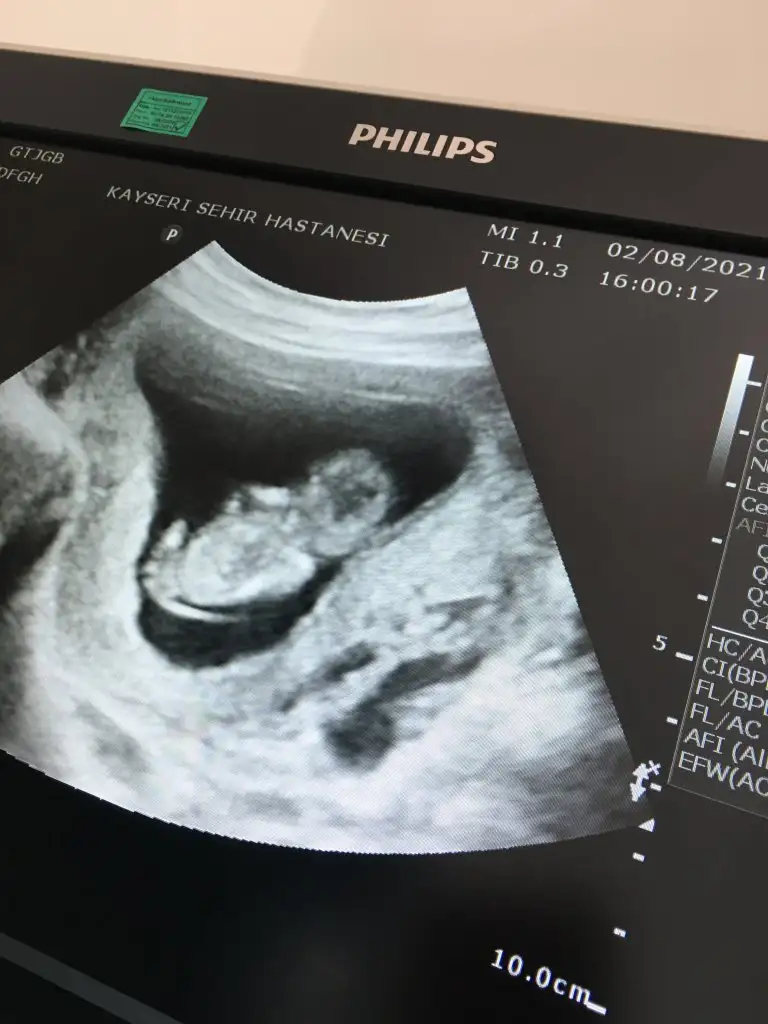

Yaa inşallah canım bu usg ablaminki ve 2 oğlu var doktor da demiş umitlenme ama kız gibiKız görünüyor![]()

Kaç haftalık USG 11 12 13 haftalar olmalı nub görünmüyor başka USG varsa

Teşekkür ederim bende öyle hissediyorumKız gibi sanki

Kizim oluyor hayirlisiyla insallahEvet burada bacak arası boş görünüyor sağlıkla gelsin prensesdiğer usg de çıkıntısı vardı